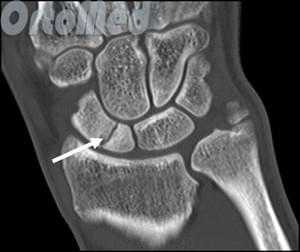

Диагностика переломов ладьевидной кости

Очень важно диагностировать перелом ладьевидной кости как можно раньше, поскольку значительная часть ладьевидной кости имеет плохое кровоснабжение и перелом может не срастись, или наступить некроз фрагмента кости (некровоснабжаемый фрагмент погибает), а это ведет к серьезным отрицательным последствиям (ограничение движений в лучезапястном суставе).

Первым и обязательным диагностическим моментом является рентгенография поврежденного участка конечности. Чаще всего рентгенография ясно показывает характер перелома ладьевидной кости.

В некоторых случаях, когда по рентгенограмме тяжело определить соотношение отломков назначается компьютерная томография лучезапястного сустава. При таком исследовании можно трехмерно увидеть поврежденную кость, что поможет в определении тактики оперативного лечения перелома.

Если перелом ладьевидной кости происходит без смещения отломков, то линию перелома на рентгенограмме можно и не увидеть. Поэтому очень важно при любой травме кисти выполнить шинирование на 10 дней. На 10 день повторить рентгенограммы кисти и, если перелом все же был, он станет четко просматриваться. Ну а далее выполняют соответствующие лечебные мероприятия (см. раздел лечение переломов ладьевидной кости).

Асептический некроз: Часть ладьевидной кости может некротизироваться (отмирает) из-за отсутствия кровоснабжения, что приводит к выраженному нарушению движений кисти, боли. Переломы в проксимальных одной трети кости, со стороны ближайшего к предплечью, более подвержены этим осложнениям. Асептический некроз становится, виден на рентгенограмме только через несколько месяцев после травмы, но это уже слишком поздно. Вот почему травмы кисти должны быть оценены врачом.